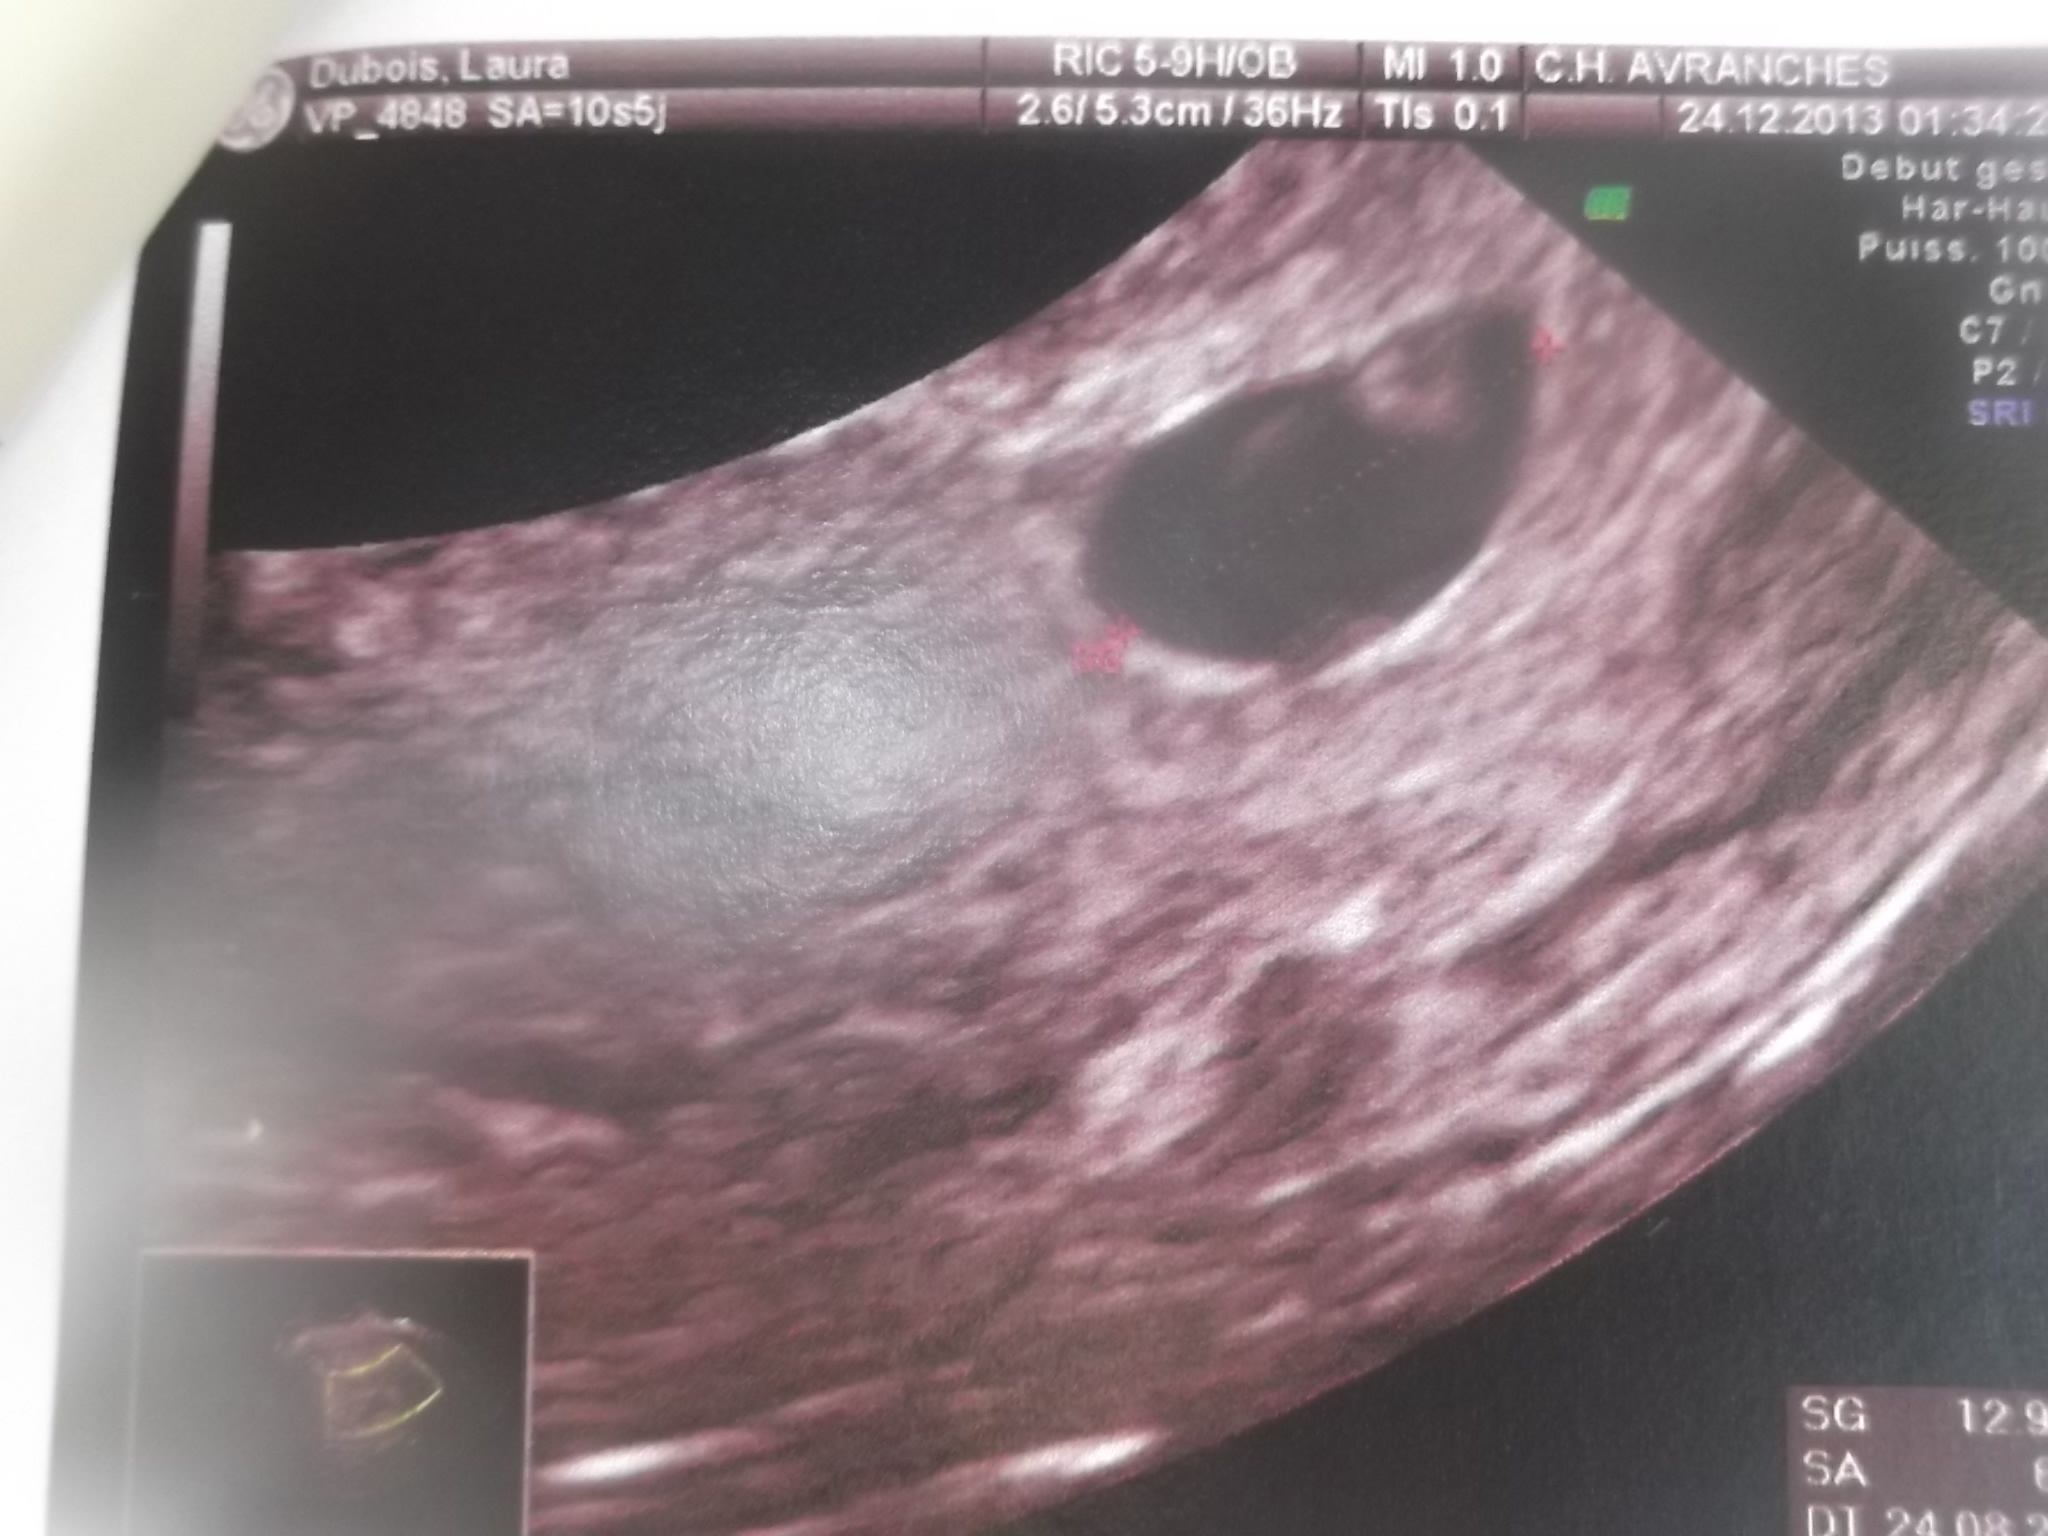

voila se que je peut te montrer et apparemnt je sui a 6sa

c'est le sac de grossesse qui mesure 12.9 mm et ce qui est dedant 2.5 mm